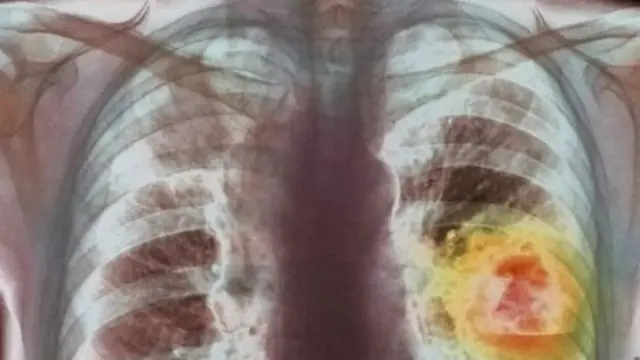

ફેફસાં કેવી રીતે કાર્ય કરે છે અને કૅન્સર તેને કેવી રીતે અસર કરે છે?

ઇમેજ સ્રોત, spl

ફેફસાં એ શ્વસનતંત્રનો એક હિસ્સો છે. તે મૂળભૂત રીતે શરીર માટેનાં ફિલ્ટર્સ છે. આપણે જે હવામાં શ્વાસ લઈએ છીએ તેમાં નાઇટ્રોજન, કાર્બન ડાયૉક્સાઇડ અને ઑક્સિજન જેવા વાયુઓ હોય છે.

ફેફસાં ઑક્સિજનને ફિલ્ટર કરે છે અને તે શરીરને આપે છે તથા બાકીના અનિચ્છનીય વાયુઓને શ્વાસ દ્વારા બહાર કાઢી નાખે છે.

ફેફસાંના કોષો અત્યંત મેટાબોલિક હોય છે. તેનો અર્થ એ કે તે સતત કાર્યરત્ હોય છે. તેમાં નુકસાન થાય ત્યારે એ કોષો જાતે પોતાનો ઉપચાર કરી લે છે.

ડૉ. અંબરીશ ચેટરજી કહે છે, “ફેફસાંએ ધૂમ્રપાન જેવી બાહ્ય ઉત્તેજનાનો સામનો કરવો પડે છે ત્યારે ફેફસાંના કોષોને નુકસાન થાય છે. આ નુકસાન લાંબા સમય સુધી વારંવાર થતું રહે છે. એ પછી કોષોની સ્વયં ઉપચારની સિસ્ટમ બદલાઈ જાય છે. તેમાં પરિવર્તન થાય છે અને જીવલેણ કોષો તરીકે પણ ઓળખાતા કૅન્સરના કોષોની રચના થાય છે. આ જીવલેણ કોષો આપણી શ્વાસ લેવાની ક્ષમતાને અવરોધે છે.”